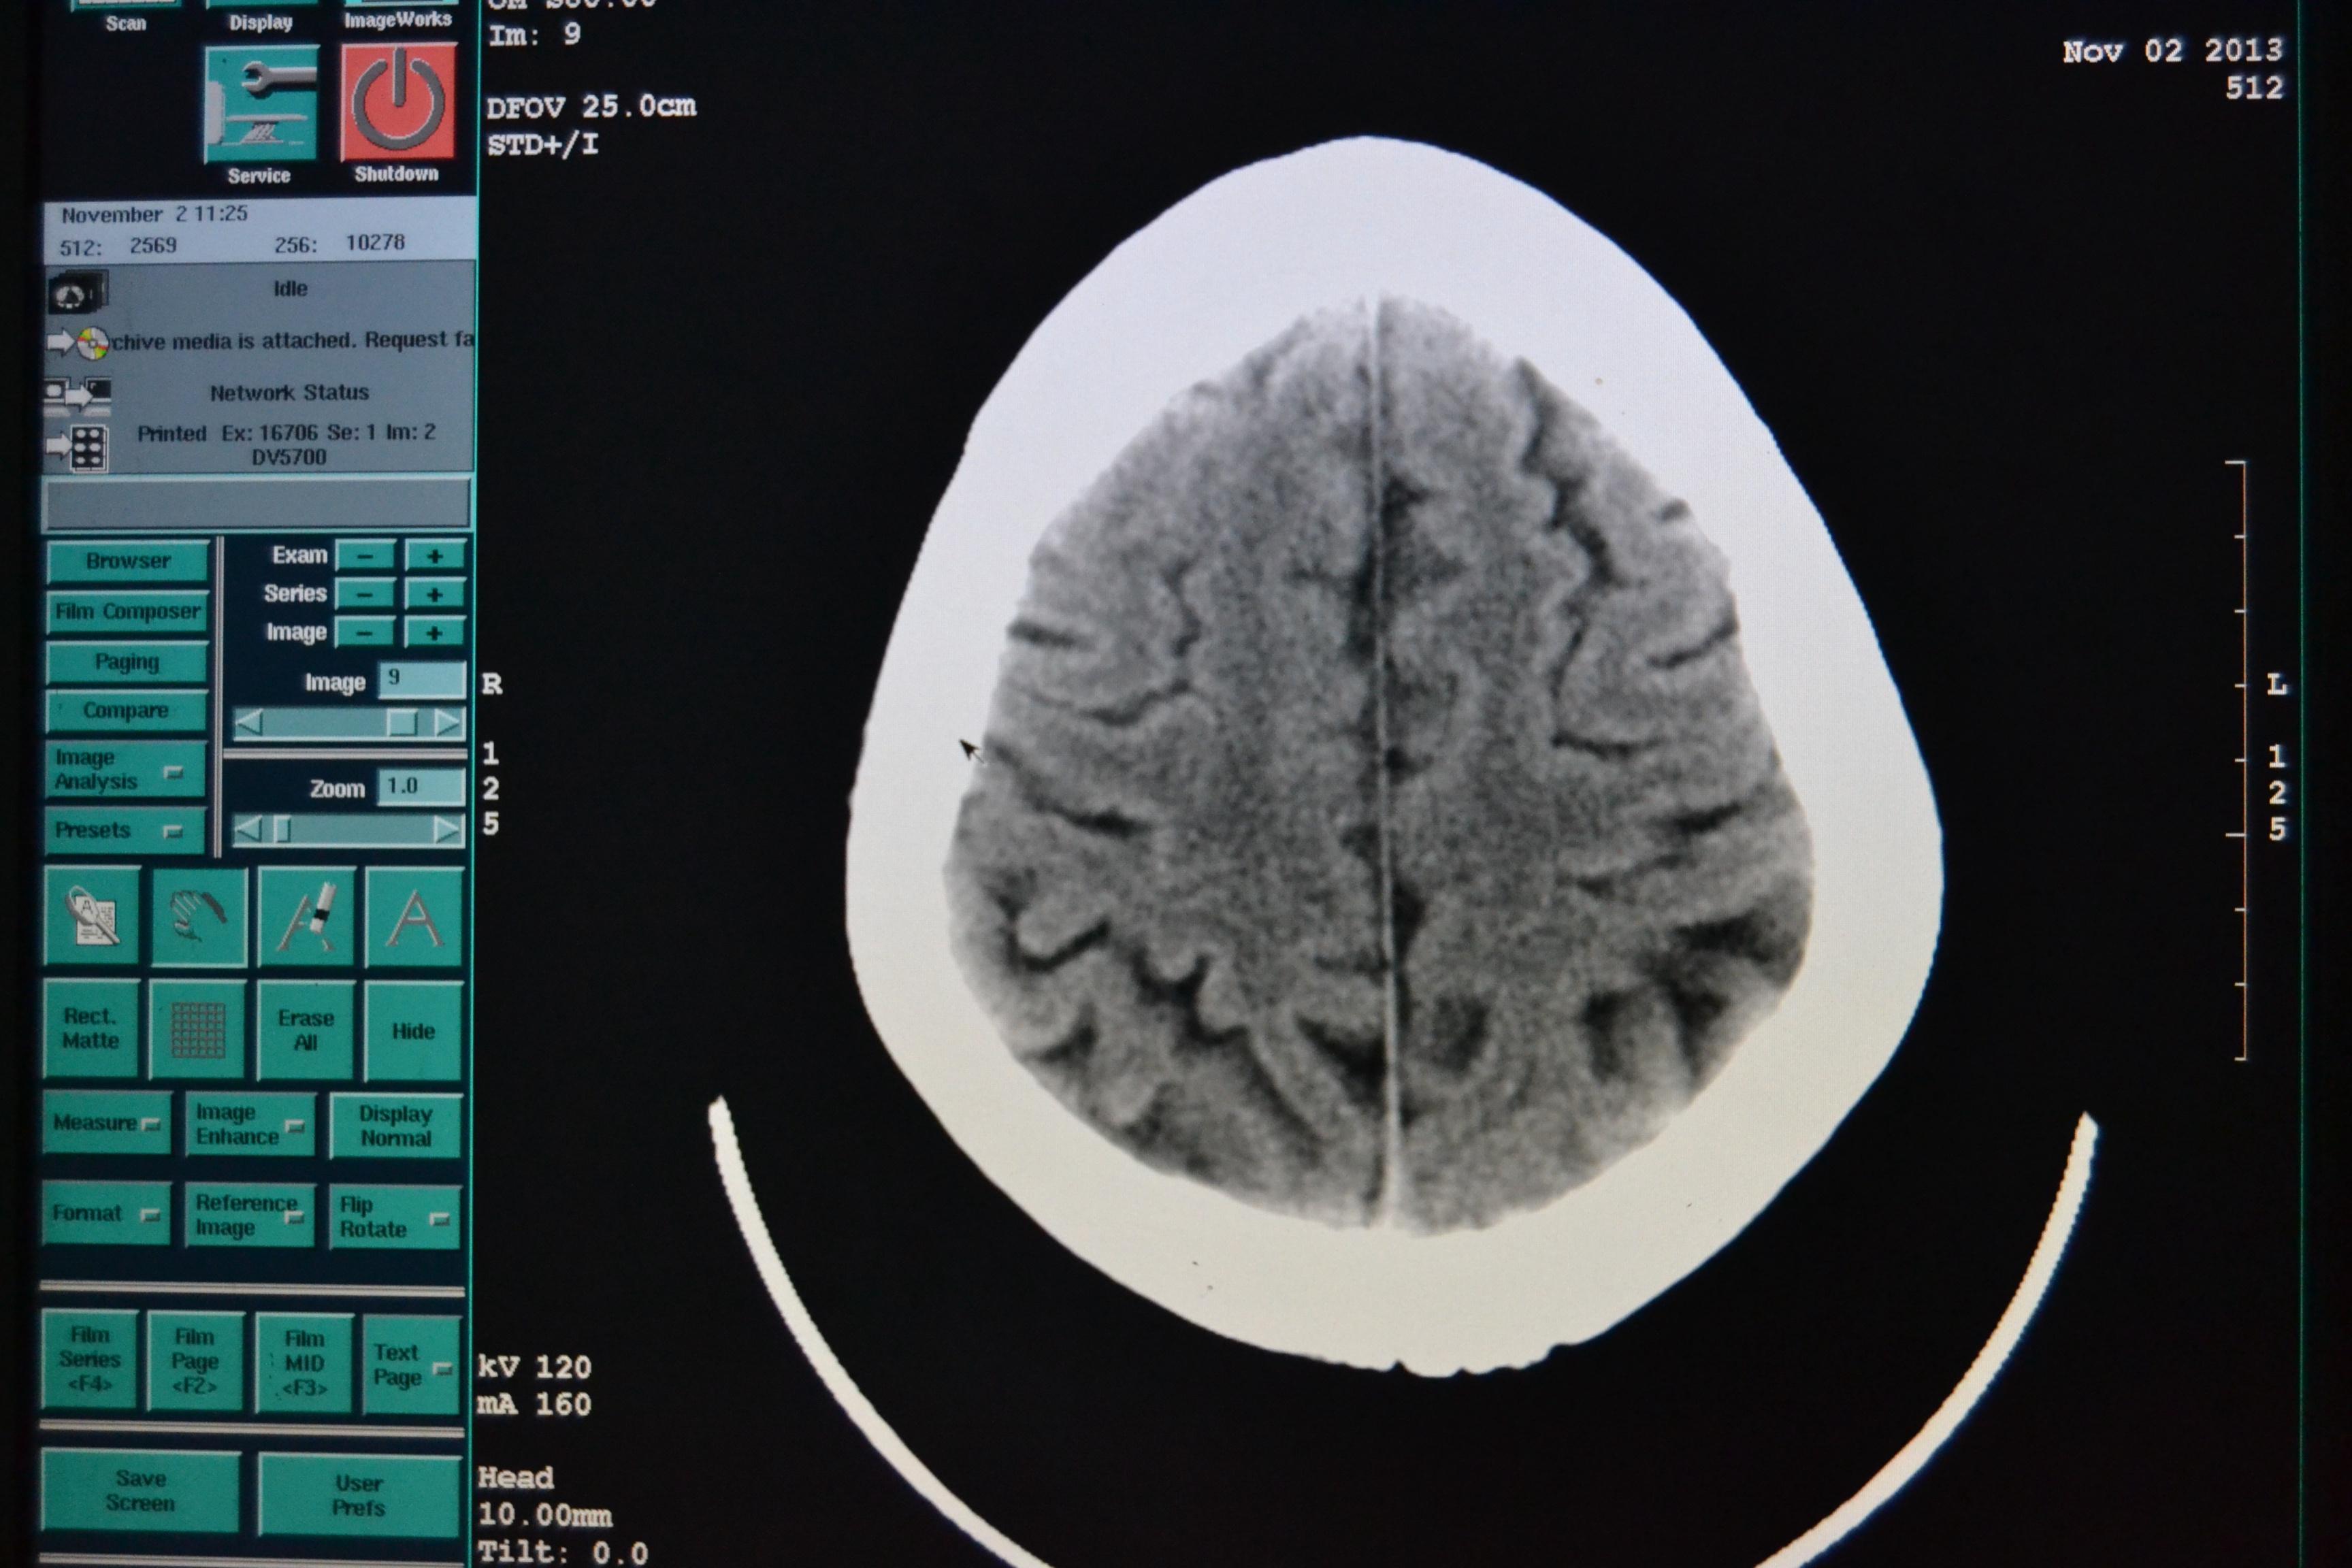

头颅ct看看透明隔

图片尺寸3456x2304